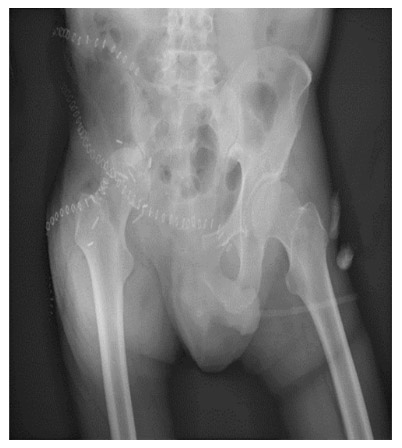

Post-surgery: The X-ray shows that the right side of the pelvis has been removed (internal hemipelvectomy).